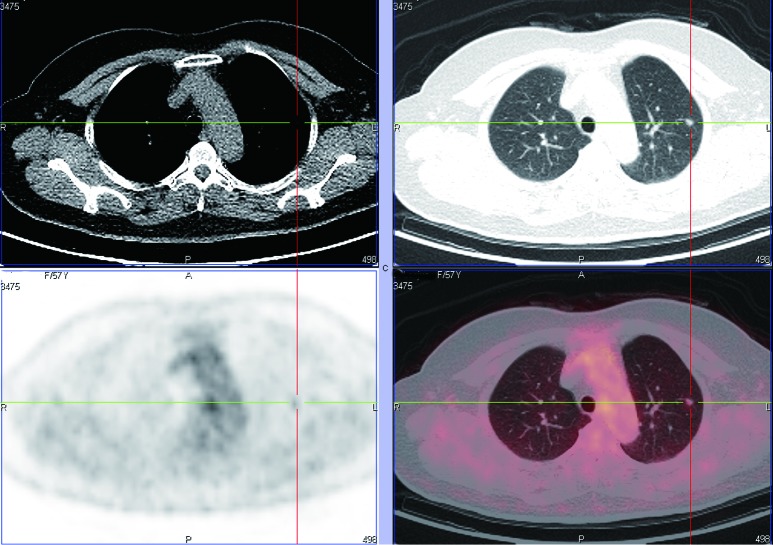

Figure 11.

PET-CT shows a case of adenocarcinoma with a SUVmax of 4.14.